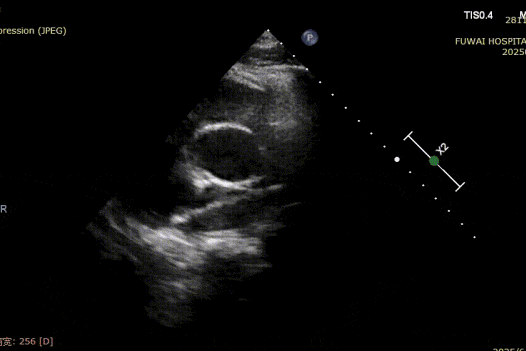

Dada a proximidade do defeito com a artéria coronária, um oclusor metálico tradicional apresentava risco de compressão, especialmente durante o esforço físico. Um oclusor biodegradável do ASD (BDASD-I 18mm) foi selecionado conseqüentemente para sua flexibilidade, mais baixo risco de ferimento mecânico a longo prazo, e capacidade para degradar no dióxido de carbono e na água após ter terminado a função do fechamento.

O procedimento foi guiado pela ETT seguindo o procedimento PAN desenvolvido no Hospital Fuwai. Essa técnica de imagem livre de radiação e em tempo real oferece visualização anatômica de alta resolução, garantindo a colocação precisa do dispositivo e minimizando as complicações-particularmente valiosas em pacientes jovens em idade reprodutiva.